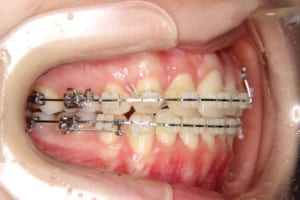

治療中

治療内容 唇側矯正装置を使用した成人矯正治療を行いました。

使用した装置 マルチブラケット装置(唇側矯正)

InVuブラケット

シルバーワイヤー

ホールディングアーチ

歯科矯正用アンカースクリュー(1本)

その他/備考 上顎右側中切歯および側切歯が、埋伏していた犬歯によって歯根吸収していました。

牽引に半年かかりました。

顎間ゴムも頑張ってくれたが期間がかかりました。